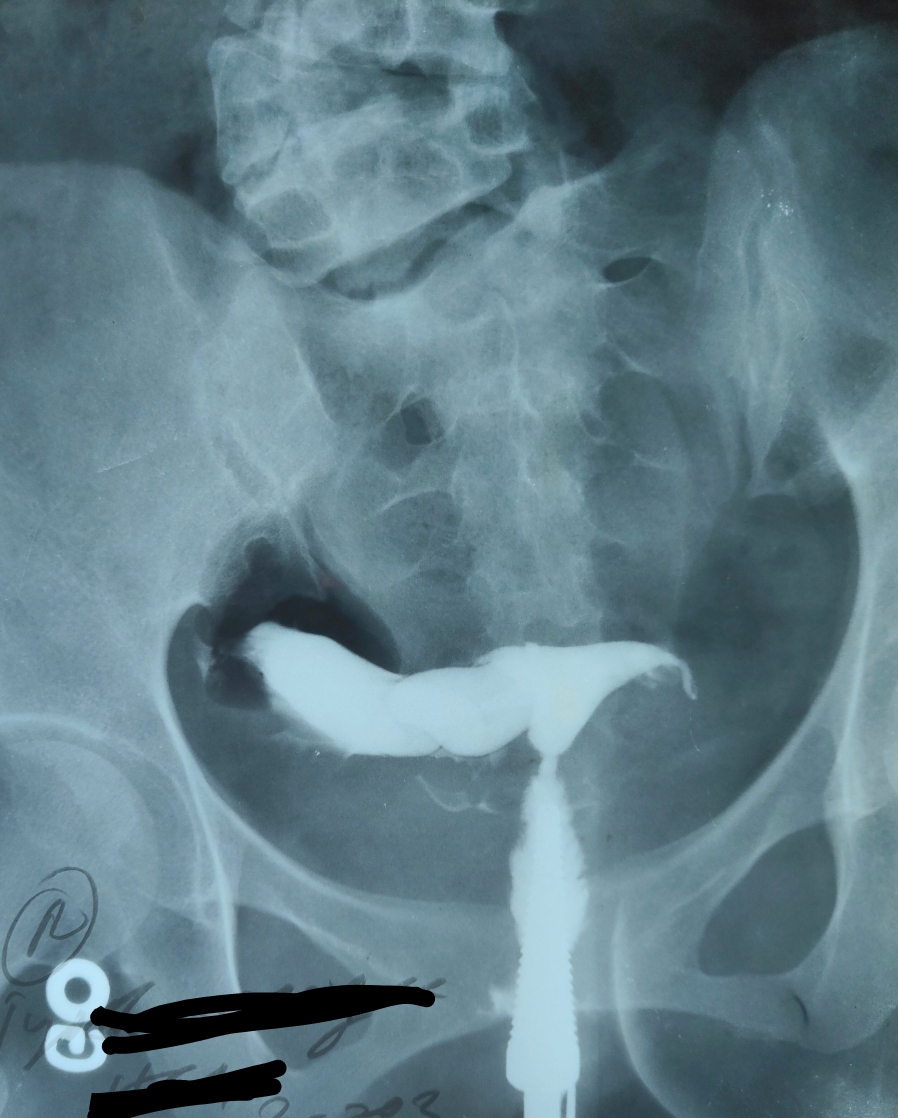

Diagnosis of hydrosalpinx by HSG. (A) Right tube hydrosalpinx. (B Tubal Hydrosalpinx It may lead to an unusual discharge, pain, and difficulty. hydrosalpinx is the medical terminology to refer to swollen fallopian tubes, filled up with fluid. The consequence of this tubal pathology is a malfunction of the tubes, which causes infertility by preventing sperm from meeting with the egg for fertilization. hydrosalpinx is a condition in which a fallopian. Tubal Hydrosalpinx.